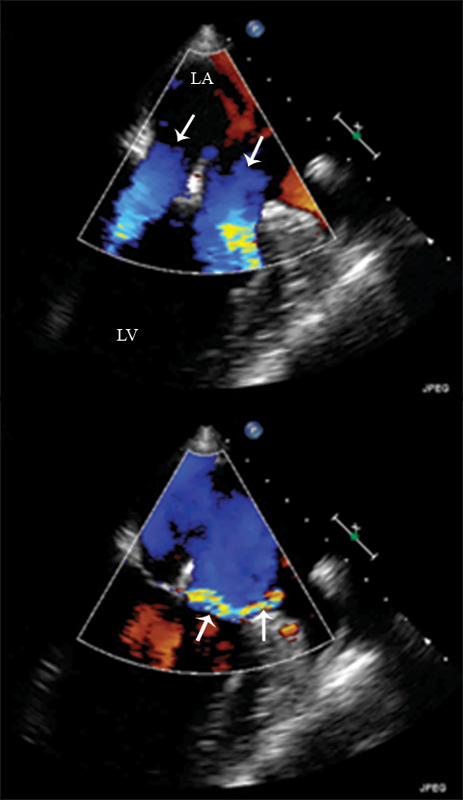

فحوصات تشخيصية لبعض امراض القلب والشرايين التاجية